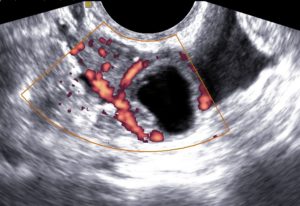

Если в органе большое количество жидкости, в том числе и кровеносных сосудов тем эхогенность её ниже, поэтому жидкостные новообразования считаются анэхогенными и на УЗИ выглядят черными.

Подобные патологии у женщин встречаются довольно часто. Возникать они могут как на дне матки, так и во внематочном пространстве. Подобные пятна во время УЗИ окрашены в черный цвет и могут иметь неоднородную структуру.

Полость этого включения пустая или наполнена жидкостью, а на мониторе представляет собой черную зону и выглядит как пятно. Края включения четкие, могут иметь ровную или неровную структуру, правильную или неправильную форму.

Анэхогенная структура внутриматочной локализации определяется при опухолевых процессах. Аваскулярные кисты отличает то, что они не имеют артерий, что говорит об отсутствии кровоснабжения.

Этот признак позволяет достоверно дифференцировать кисту матки от других новообразований. Обнаруженное включение определяется, как пустое образование с ровными краями или неправильной формы.

Внутри кисты, как правило, содержится жидкость.